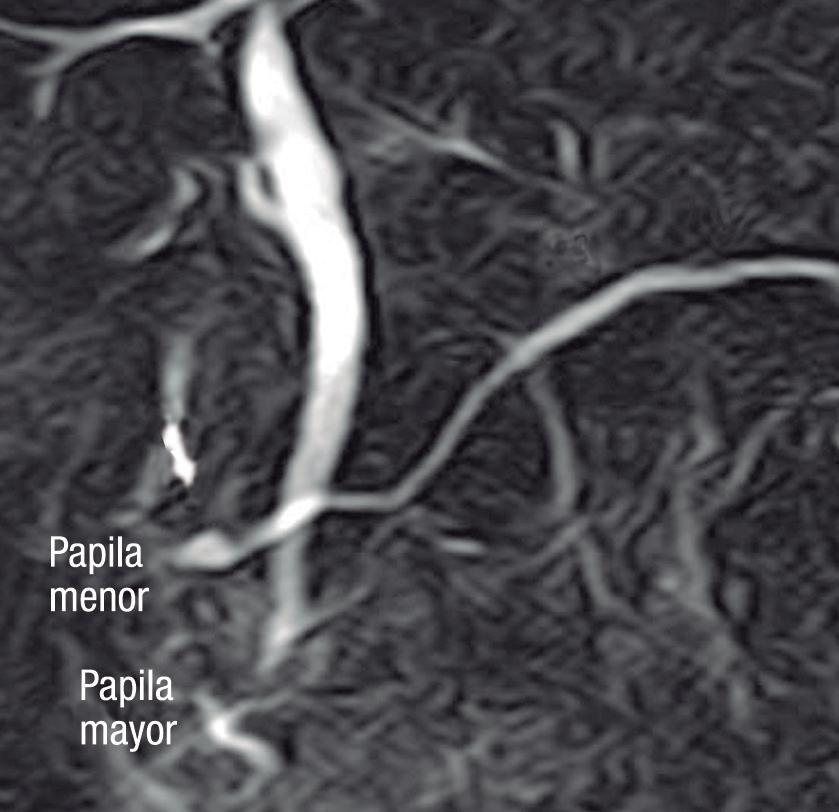

Conducto biliopancreático común largo

La unión entre el conducto colédoco y el conducto pancreático ocurre de diversas maneras, la mayoría son consideradas variantes normales y no tienen implicancias clínicas. Suelen confluir en un canal común con una longitud menor a los 5 mm y con un ángulo variable, alternativamente puede existir un ingreso al duodeno de ambos conductos por separado. En el canal común biliopancreático largo existe una unión precoz del colédoco con el conducto pancreático, con confluencia proximal al esfínter de Oddi por fuera de la pared duodenal. Para su diagnóstico se requiere una distancia mayor o igual a 15 mm entre la papila mayor y la confluencia de ambos conductos (Figura 6). Este conducto común largo permite el reflujo de las secreciones pancreáticas al colédoco, aumentando la presión intraductal y favoreciendo el desarrollo de quistes coledocianos. También favorece el reflujo de bilis hacia el conducto pancreático y, como consecuencia, predispone a la PA y PAR. 14,15

Figura 7. Conducto biliopancreático común largo

La flecha blanca señala la unión precoz del conducto colédoco con el conducto pancreático principal, alejada de la pared duodenal - papila mayor (cabeza de flecha), conformando un conducto biliopancreático común largo (> 15 mm).

A) Colangio-RM. La flecha señala la unión precoz del conducto colédoco con el conducto de Wirsung, alejado de la pared duodenal, conformando un conducto biliopancreático común largo. Se observa, como complicación, el desarrollo de un quiste de colédoco (cabezas de flecha). B) Colangio-RM magnificada. Medición de la distancia entre la pared duodenal, en el sitio de la papila mayor y la unión de los conductos colédoco y pancreático. C) Resonancia magnética, secuencia T1 con gadolinio, plano coronal. Unión de los conductos (flecha). Pared duodenal - papila mayor (cabeza de flecha).